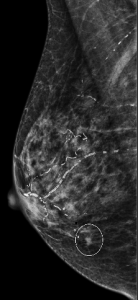

B. BI-RADS 2 (Benign); Recommend one year follow-up

Explanation: A mass with this type of popcorn-like calcifications is almost certainly a fibroadenoma and benign. Having prior mammograms which demonstrate little or no change over time can increase your confidence.